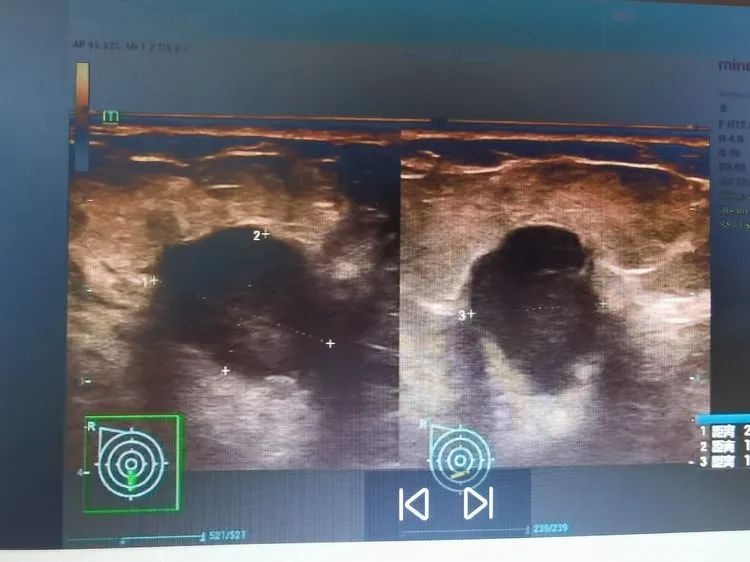

故事发生在数月前,刚刚50岁出头的陈女士在一次体检中,意外发现右侧乳腺包块。虽然包块不疼不痒也不大,但是为了明确性质,陈女士和家人来到广济医院做进一步检查。安静的彩超室里,随着探头的游走,段林主任仔细捕捉着屏幕上每一处变化,经验丰富的她很快发现了异常。仔细辨别后,她截取典型病变的画面后,给出超声诊断:右乳实性低回声结节22*16*16mm,BI-RADS4b类,右侧腋窝多发低回声结节。随后,段主任将彩超影像的诊断结果告知家人和接诊科室,建议进一步检查。得知诊断结果,陈女士一家人心中五味杂陈。

原来,超声诊断上的“BI-RADS4b”代表着“不太好”。专家解释道,乳腺BI-RADS分级是根据肿物的大小、边界是否光滑、肿物内是否有血运、钙化及同侧的腋窝是否出现异常肿大的淋巴结进行的分类。一共分0-6七个等级。0-3级,绝大多数是良性病变,4级有一定恶变的可能。4级中又分为4a、4b、4c三个亚级,恶性程度逐渐增加,恶性危险性3%—94%。5-6级基本属于恶性,要积极进行手术切除,并配合术后的综合疗法,提高肿瘤的治疗效果。